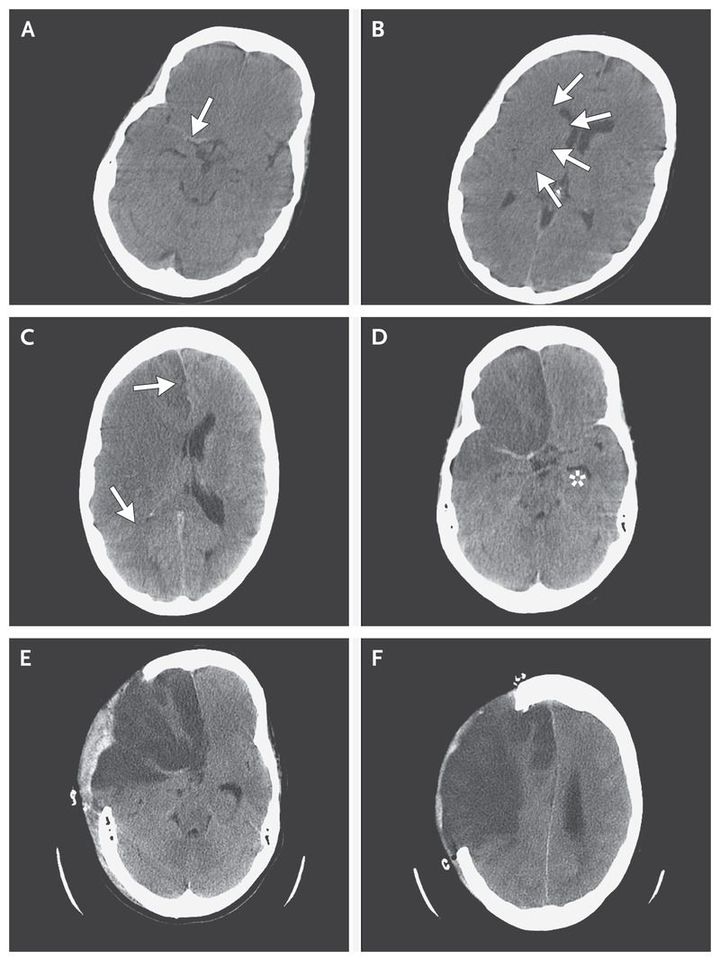

A 47-year-old woman with a history of migraine was admitted to the hospital with acute-onset headache on the left side of her head and mild weakness of her left arm. Computed tomography (CT) of the brain without the use of contrast material was performed 5 hours after symptom onset and showed linear areas of hyperdensity in the first segment of the right middle cerebral artery (Panel A, arrow) and the first segment of the anterior cerebral artery. There were early signs of cerebral edema, including subtle low attenuation with loss of gray–white differentiation and effacement of sulci in both the right middle-cerebral-artery and anterior-cerebral-artery territories (Panel B, arrows). Four hours later, the patient became drowsy, and complete paralysis of the left side developed. A CT scan of the brain 9 hours after symptom onset showed large, nonhemorrhagic infarcts in the middle-cerebral-artery and anterior-cerebral-artery territories, with increased edema, mild right-to-left midline shift (Panel C, arrows), and some trapping of the left lateral ventricle (Panel D, asterisk). A total of 21 hours after symptom onset, the patient underwent decompressive craniectomy of the frontoparietal region (Panels E and F). She had a gradual recovery but died 6 weeks later from pneumonia.